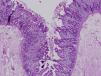

Secretory diarrhoea developed in the first month of life in all 3 patients. One patient was female and the other 2 were male. The former patient was of Ecuadorean descent and the other 2 were brothers of Moroccan descent born to consanguineous parents. All had been born to term and had adequate birth weights. The prenatal ultrasound examinations had been normal. None of the patients presented with atresia or punctuated keratitis. The immunological study was unremarkable. Histological examination of the intestinal mucosa revealed villous shortening and focal crowding of enterocytes resembling tufts (Figs. 1 and 2). The presence of a homozygous mutation in the EpCAM gene was confirmed in patients 2 and 3, with detection of a 17-base pair intragenic deletion (c.352_368del, NM_002354,2). The first patient did not undergo genetic testing.

Its diagnosis is based on the typical histological features of this disease. Examination with light microscopy reveals marked villous atrophy with crypt hyperplasia in the absence of inflammatory infiltrate in the lamina propria. The characteristic finding is the clustering of closely packed enterocytes, which results in stunted surface projections and form the “tufts” that the disease is known for.1 On examination with electron microscopy, the ultrastructural elements associated with enterocytes tufting include a slight shortening of the brush border and an increase in the desmosome length and number. Immunostaining for MOC31 normally stains the mucosal epithelium but not the lamina propria or vessels. In cases of IED, there is a complete absence of staining in the epithelial surface, crypts and tufts. Some patients present with associated dysmorphic features, oesophageal atresia or choanal or anorectal atresia.4 And up to 60% of patients have associated punctuated keratitis.4